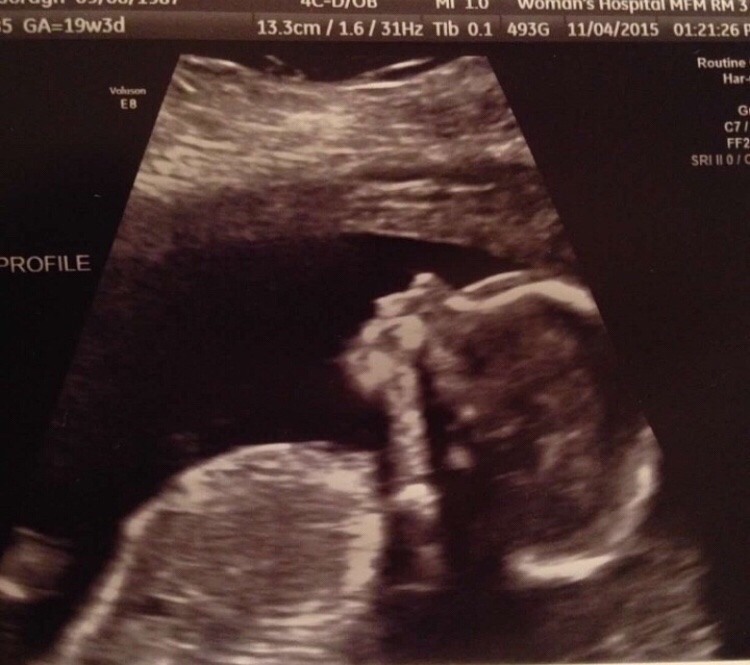

We walk inside, wait a while, finally see the doctor. He then proceeds with the ultrasound and we let him know that we wanted to know the baby’s gender. As soon as the monitor went on my belly… it was clear as day.. a boy part! We both just laughed so hard as soon as the doctor confirmed what we thought we saw! Brandon’s exact words were “we are having a little dude!” I couldn’t believe it! I was so excited! And after all of that fear and worry about this, such a sweet result! My heart was happy! It’s like all of a sudden, this sweet baby had an identity and we could prepare and be excited about this baby! We left the hospital and went home to surprise friends and family with a little scavenger hunt! Everyone was so excited and I think a bit nervous that maybe I was sad. I don’t think it had taken very long for everyone to see that I was quite alright.